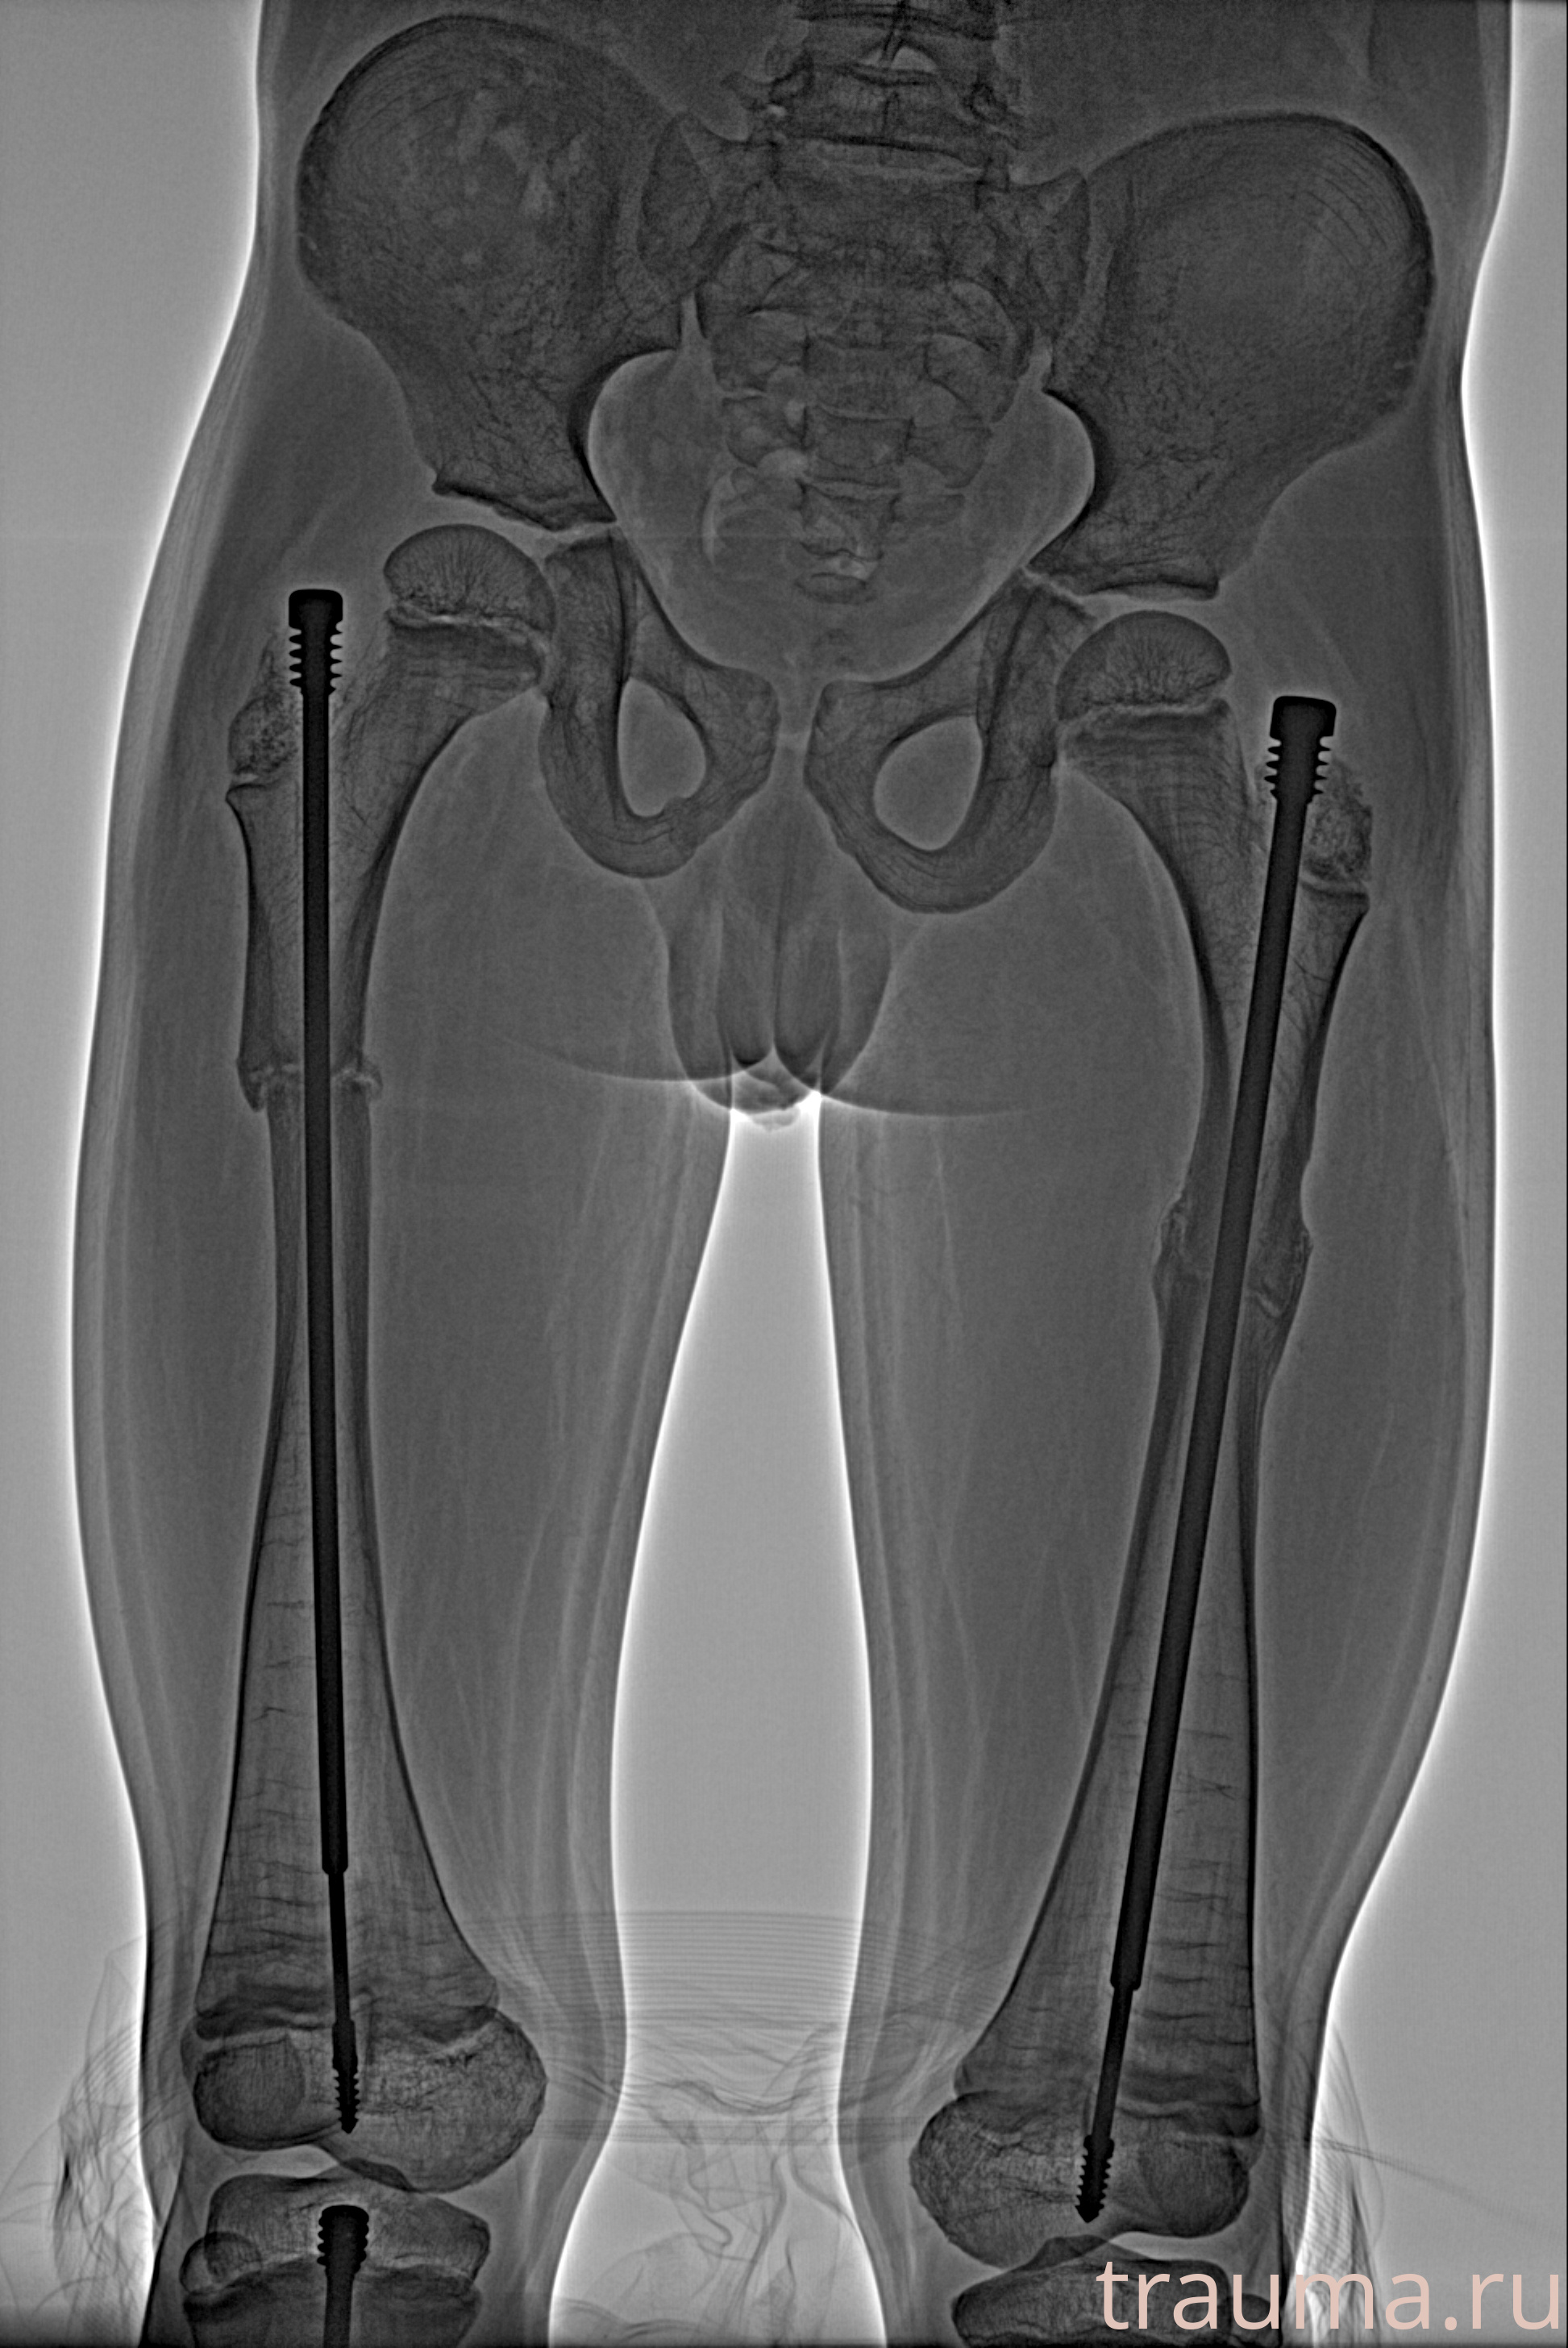

Рентгенограммы

Рентген на дому: по вашему адресу приезжает врач-рентгенолог, травматолог-ортопед с мобильным рентгеновским аппаратом, проводит диагностику травмы или заболевания, делает необходимые рентгенограммы, дает рекомендации по дальнейшему лечению. Получить качественные снимки в домашних условиях возможно благодаря уникальной методике, разработанной МосРентген Центром для института  Склифосовского